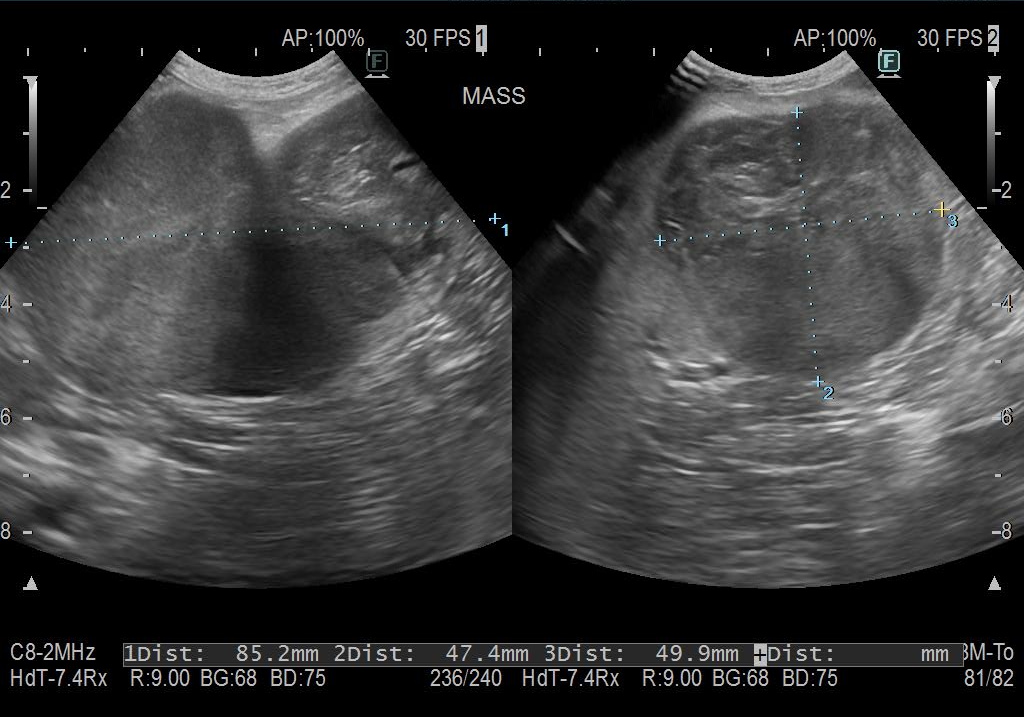

レントゲン検査、超音波検査にて脾臓に大きなしこりが見つかりました。

摘出した脾臓です。

表と裏に大きなしこりを形成していました。

破裂した部分に脂肪が癒着して大出血を防いでいたようです。おかげで致命傷にならずに済んだのかもしれません。

病理組織検査を行ってもらったところ、結節性過形成(腫瘍ではない)でしたので、摘出した後は問題ないとのことでした。